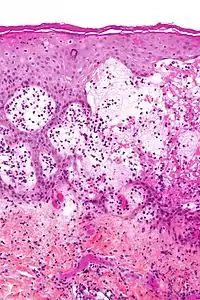

Micrograph of gestational pemphigoid showing the characteristic subepidermal blisters and abundant eosinophils. HPS stain.